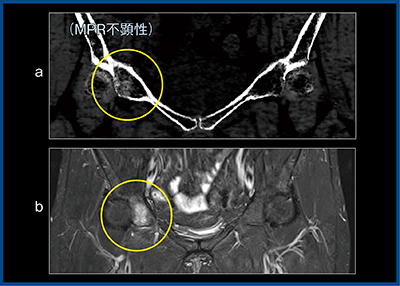

症例3は,転倒による股関節の疼痛を訴える患者で,135kVpのMPR画像では骨折線を認められなかったため,BBI解析を施行した。BBIでは,右股関節と骨盤臼蓋部分の高吸収域(○)をとらえている(図3 a)。さらに,MRI検査を行ったところ,脂肪抑制T2強調画像でBBI同様,右の骨盤臼蓋部分が高信号(○)を呈し,骨挫傷と判明した(図3 b)。

図3 症例3:股関節痛(骨挫傷)

a:BBI b:脂肪抑制T2強調画像